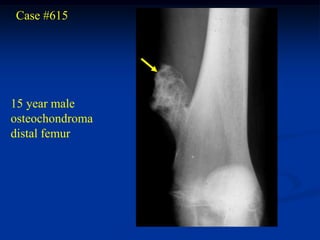

Case #615

15 year male

osteochondroma

distal femur

cap

Cut specimen in path lab

cartilage cap

cartilage

Photomic